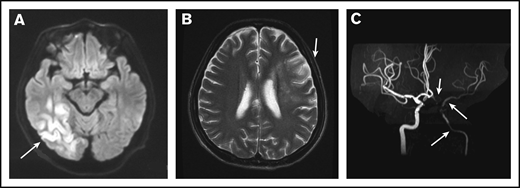

Among 41 IS cases, 19 (46.3%) were multifocal, including 12 bilateral and 7 unilateral. Cerebral vessels were evaluated in only 8 patients via magnetic resonance angiography (MRA) or computed tomography angiography (CTA) (Figure 2A-C). Seven (87.5%) of 8 patients were documented to have cerebral vasculopathy; 3 patients were shown to have multiple and bilateral cerebral artery stenosis or occlusion, including the internal carotid artery, 2 with unilateral internal carotid artery stenosis, 1 with unilateral middle cerebral artery stenosis, and 1 with unilateral posterior cerebral artery stenosis. Cerebral venous sinus thrombosis was demonstrated in 1 patient.

MRI and MRA for a patient with POEMS syndrome and IS. (A) MRI of the brain showed a cerebral infarction of the right temporal occipital lobe (white arrow). (B) A second MRI showed a new focal lesion of cerebral infarction near the left centrum semiovale 1 month later (white arrow). (C) MRA showed severe stenosis of the left intracranial internal carotid artery, left middle cerebral artery, and left anterior artery (white arrows).